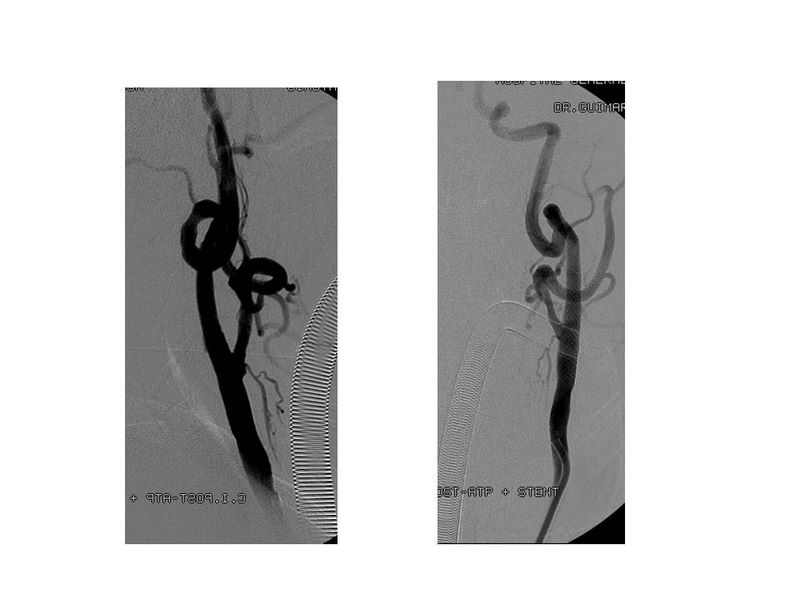

Otro Stent Carotideo